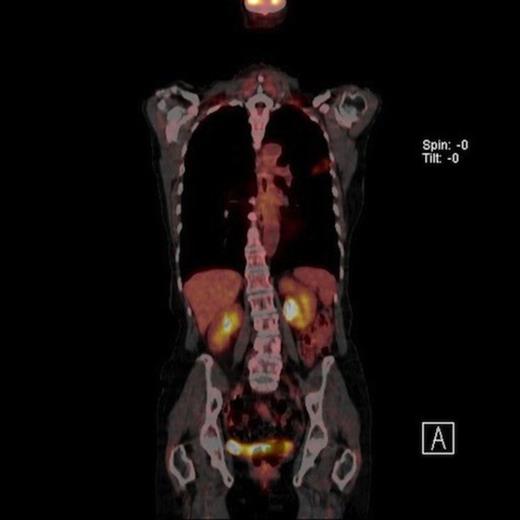

A 61-year-old female smoker (42 pack years) was found to have left upper zone shadowing on chest X ray following a history of weight loss. Her performance status was 1 with a Forced expiratory volume in one second (FEV1) of 1.94 Litres. Positron emission tomography in conjunction with computed tomography (PET-CT) showed two nodules in the left upper lobe. There was a 2cm spiculated lesion in the anterior segment with a Standardised Uptake Value (SUV) max of 5.6 units (Fig 1A) and a 2.2 cm cavitating lesion in the apico-posterior segment with a SUV max of 2.7 units (Fig 1B). There was no radiologic evidence of mediastinal lymhadenopathy or distant metastases.

Coronal view PET CT scan of a high uptake nodule in the left upper lobe